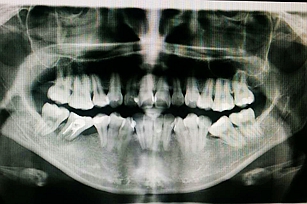

- 下頜阻生牙的阻力分析

- 5-阻生牙拔除應(yīng)用解剖和阻力分析、臨床分類